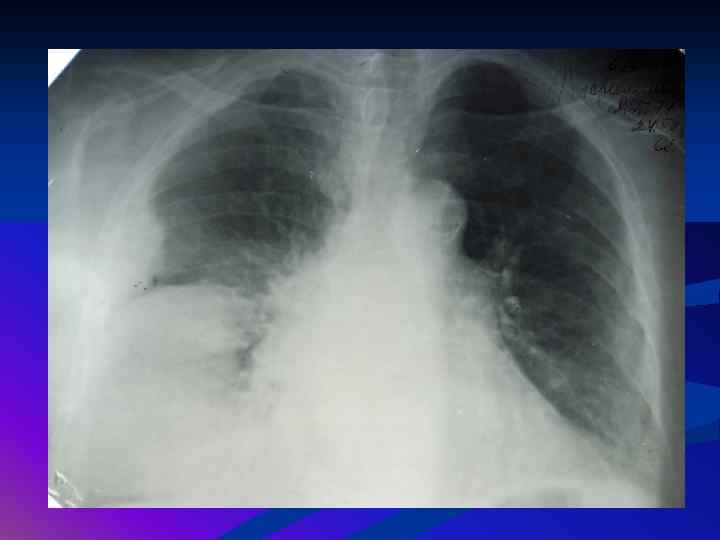

Диагностика плеврального выпота: что нужно знать